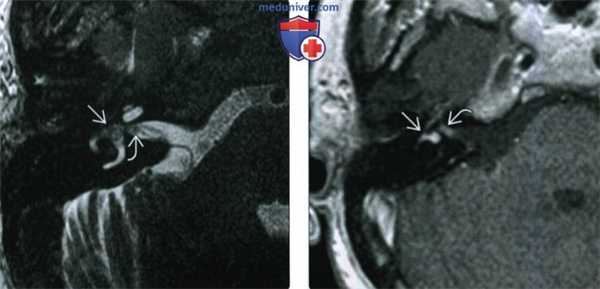

(Слева) При аксиальной МРТ Т2 ВИ определяется ИЛШ трансмакулярного типа в виде материала с интенсивностью сигнала, соответствующей мягким тканям, заполняющего преддверие и распространяющегося вдоль ветвей преддверного нерва до дна дистальных отделов внутреннего слухового канала (ВСК).

(Справа) При аксиальной МРТ Т1ВИ у этого же пациента определяется контрастное усиление интравестибулярной и дистальной интраканаликулярной части этой трансмакулярной шванномы. Минимальное отличие параметров контрастного усиления обусловлено эффектом усреднения объема.